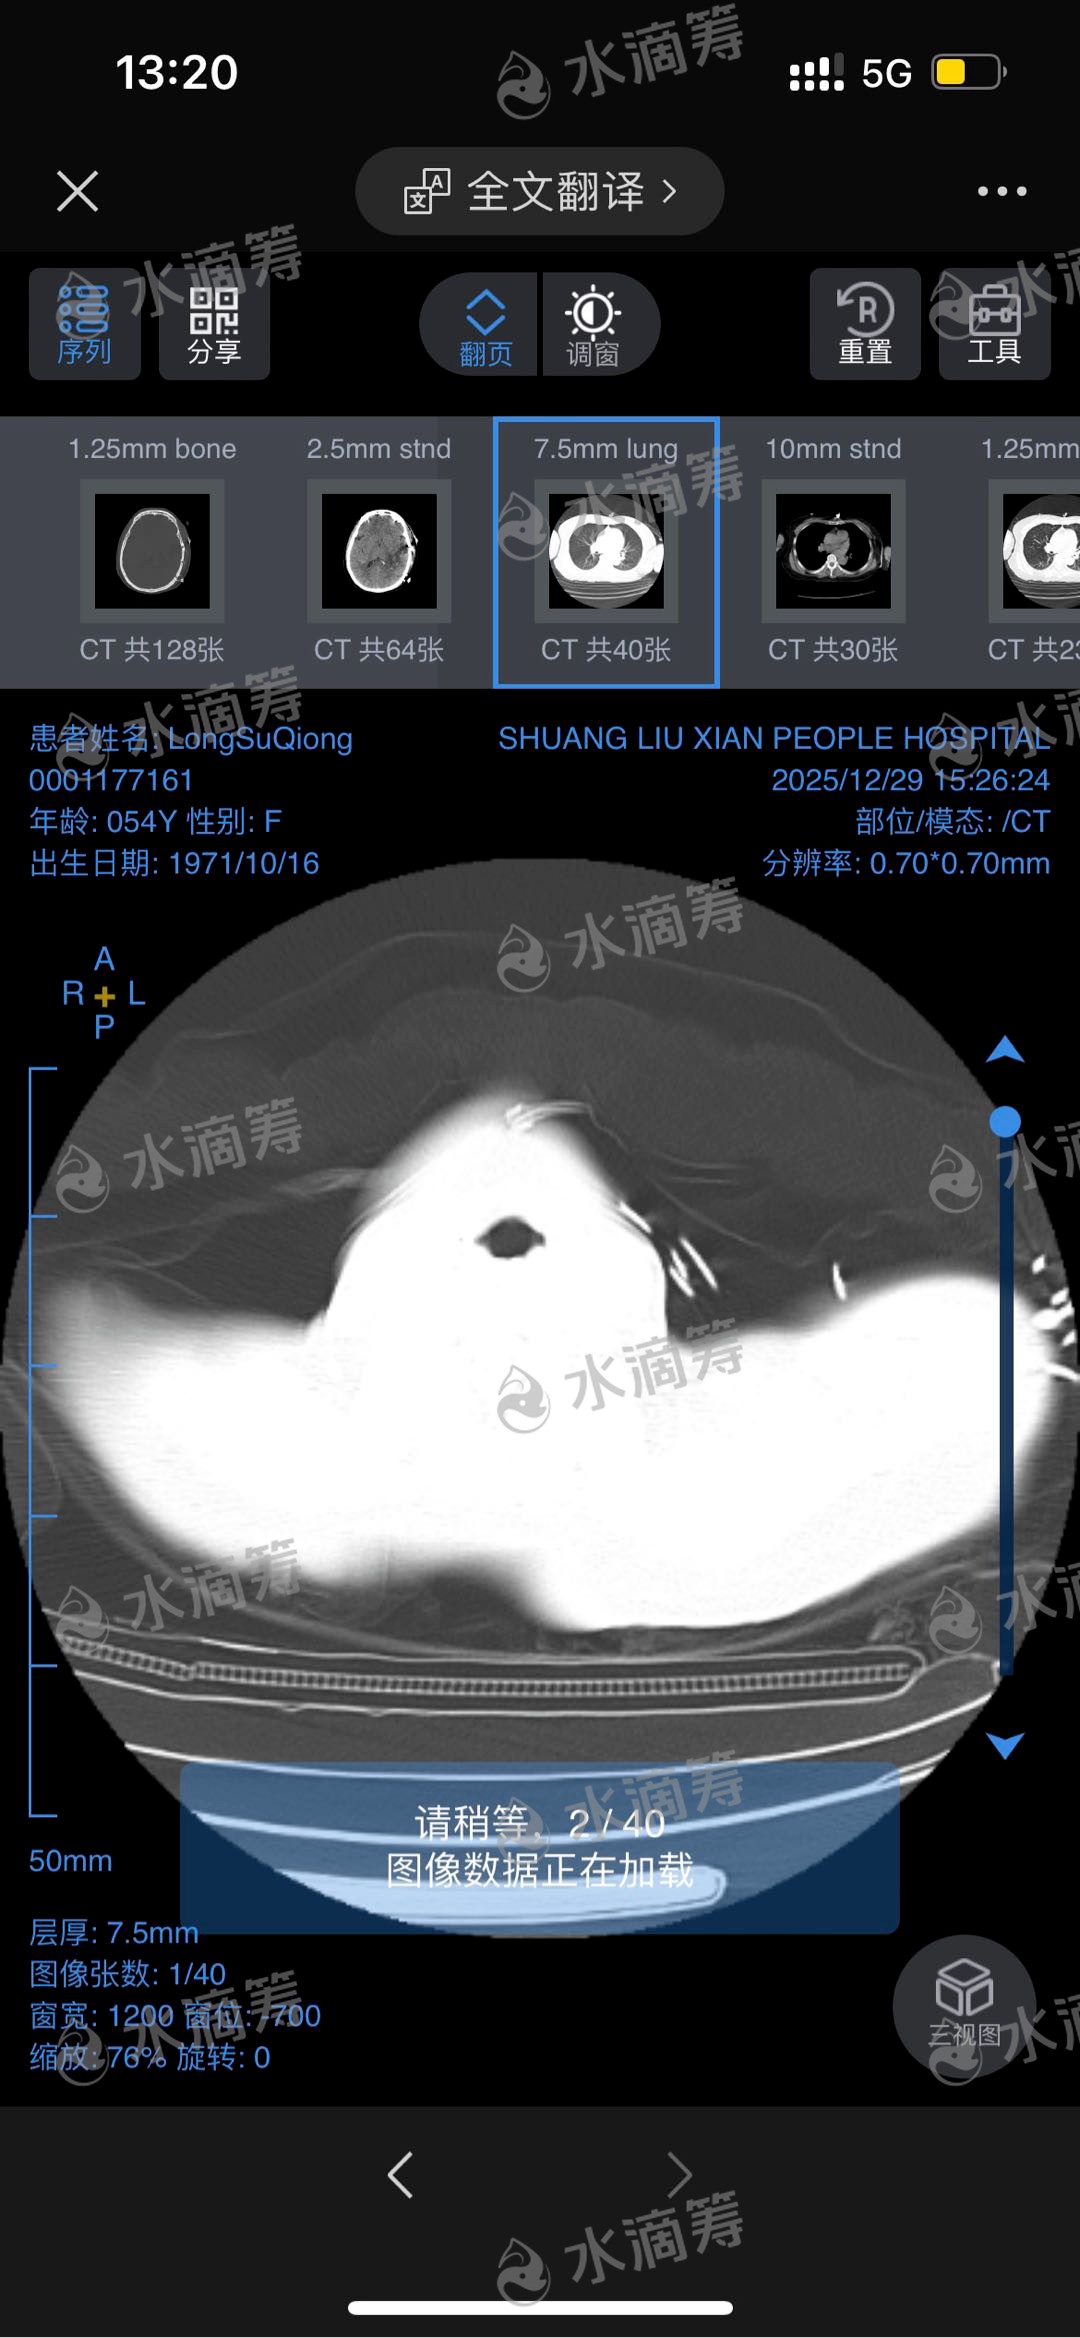

家母龙素琼,现年54岁,常年在成都市务工,以微薄收入支撑家庭。2025年12月27日上午,她突发脑出血,被紧急送往成都市双流区第一人民医院抢救。经紧急手术后,病情却未见好转,反而并发脑水肿及肺部感染,至今仍在ICU重症监护室接受治疗。ICU的监护与治疗每日开销巨大,后续康复调理所需费用亦不菲,这对本就艰难的家庭而言,无疑是雪上加霜。